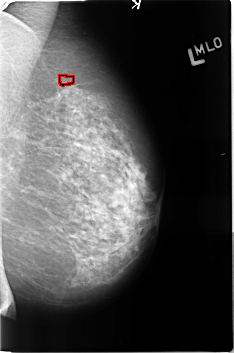

B_3361_1.LEFT_MLO

FILE: B_3361_1.LEFT_MLO.OVERLAY

TOTAL_ABNORMALITIES 1

ABNORMALITY 1

LESION_TYPE CALCIFICATION TYPE PUNCTATE DISTRIBUTION CLUSTERED

ASSESSMENT 4

SUBTLETY 3

PATHOLOGY BENIGN

TOTAL_OUTLINES 1

BOUNDARY